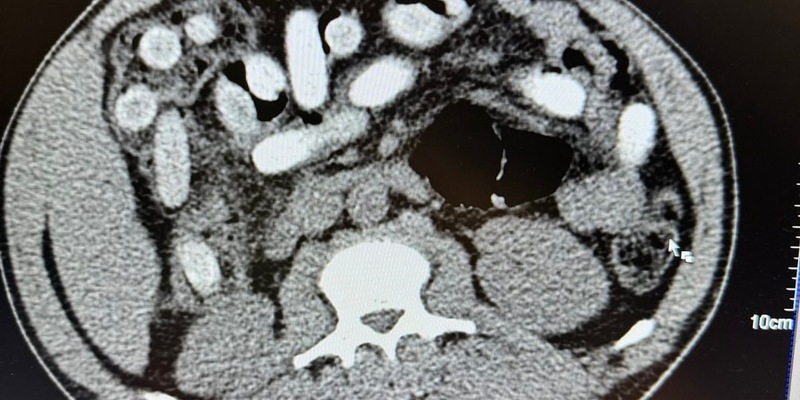

"Die Röntgenaufnahme in einem nahegelegenen Krankenhaus bestätigte letztendlich den Verdacht meiner Kollegen. Der komplette Magen-Darm-Trakt des Mannes war voll mit Drogenpäckchen, sogenannten Bodypacks. In der Größe und Form sind diese mit Datteln vergleichbar. Nach dem Ausscheiden der Drogen war klar, der Mann hatte 111 dieser mit Kokain gefüllten Bodypacks geschluckt. Rund 1,3 Kilogramm Kokain versteckt im Körper ist für uns ein neuer trauriger Rekord. Das Risiko beim Körperschmuggel ist enorm. Wenn nur ein Päckchen im Körper aufgeht, ist das Leben des Mannes nicht mehr zu retten, selbst wenn ein Arzt direkt danebensteht", so Jens Ahland, Pressesprecher des Hauptzollamts Köln.